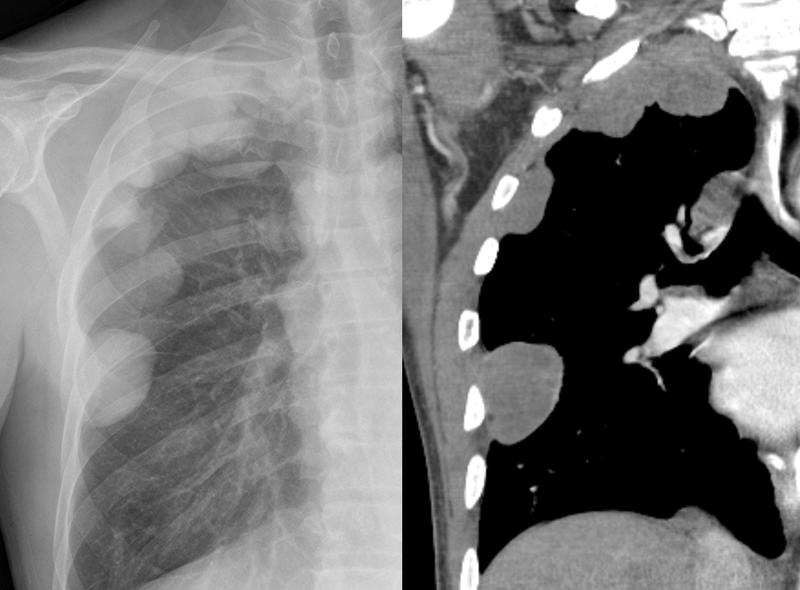

Pleural

Mesothelioma